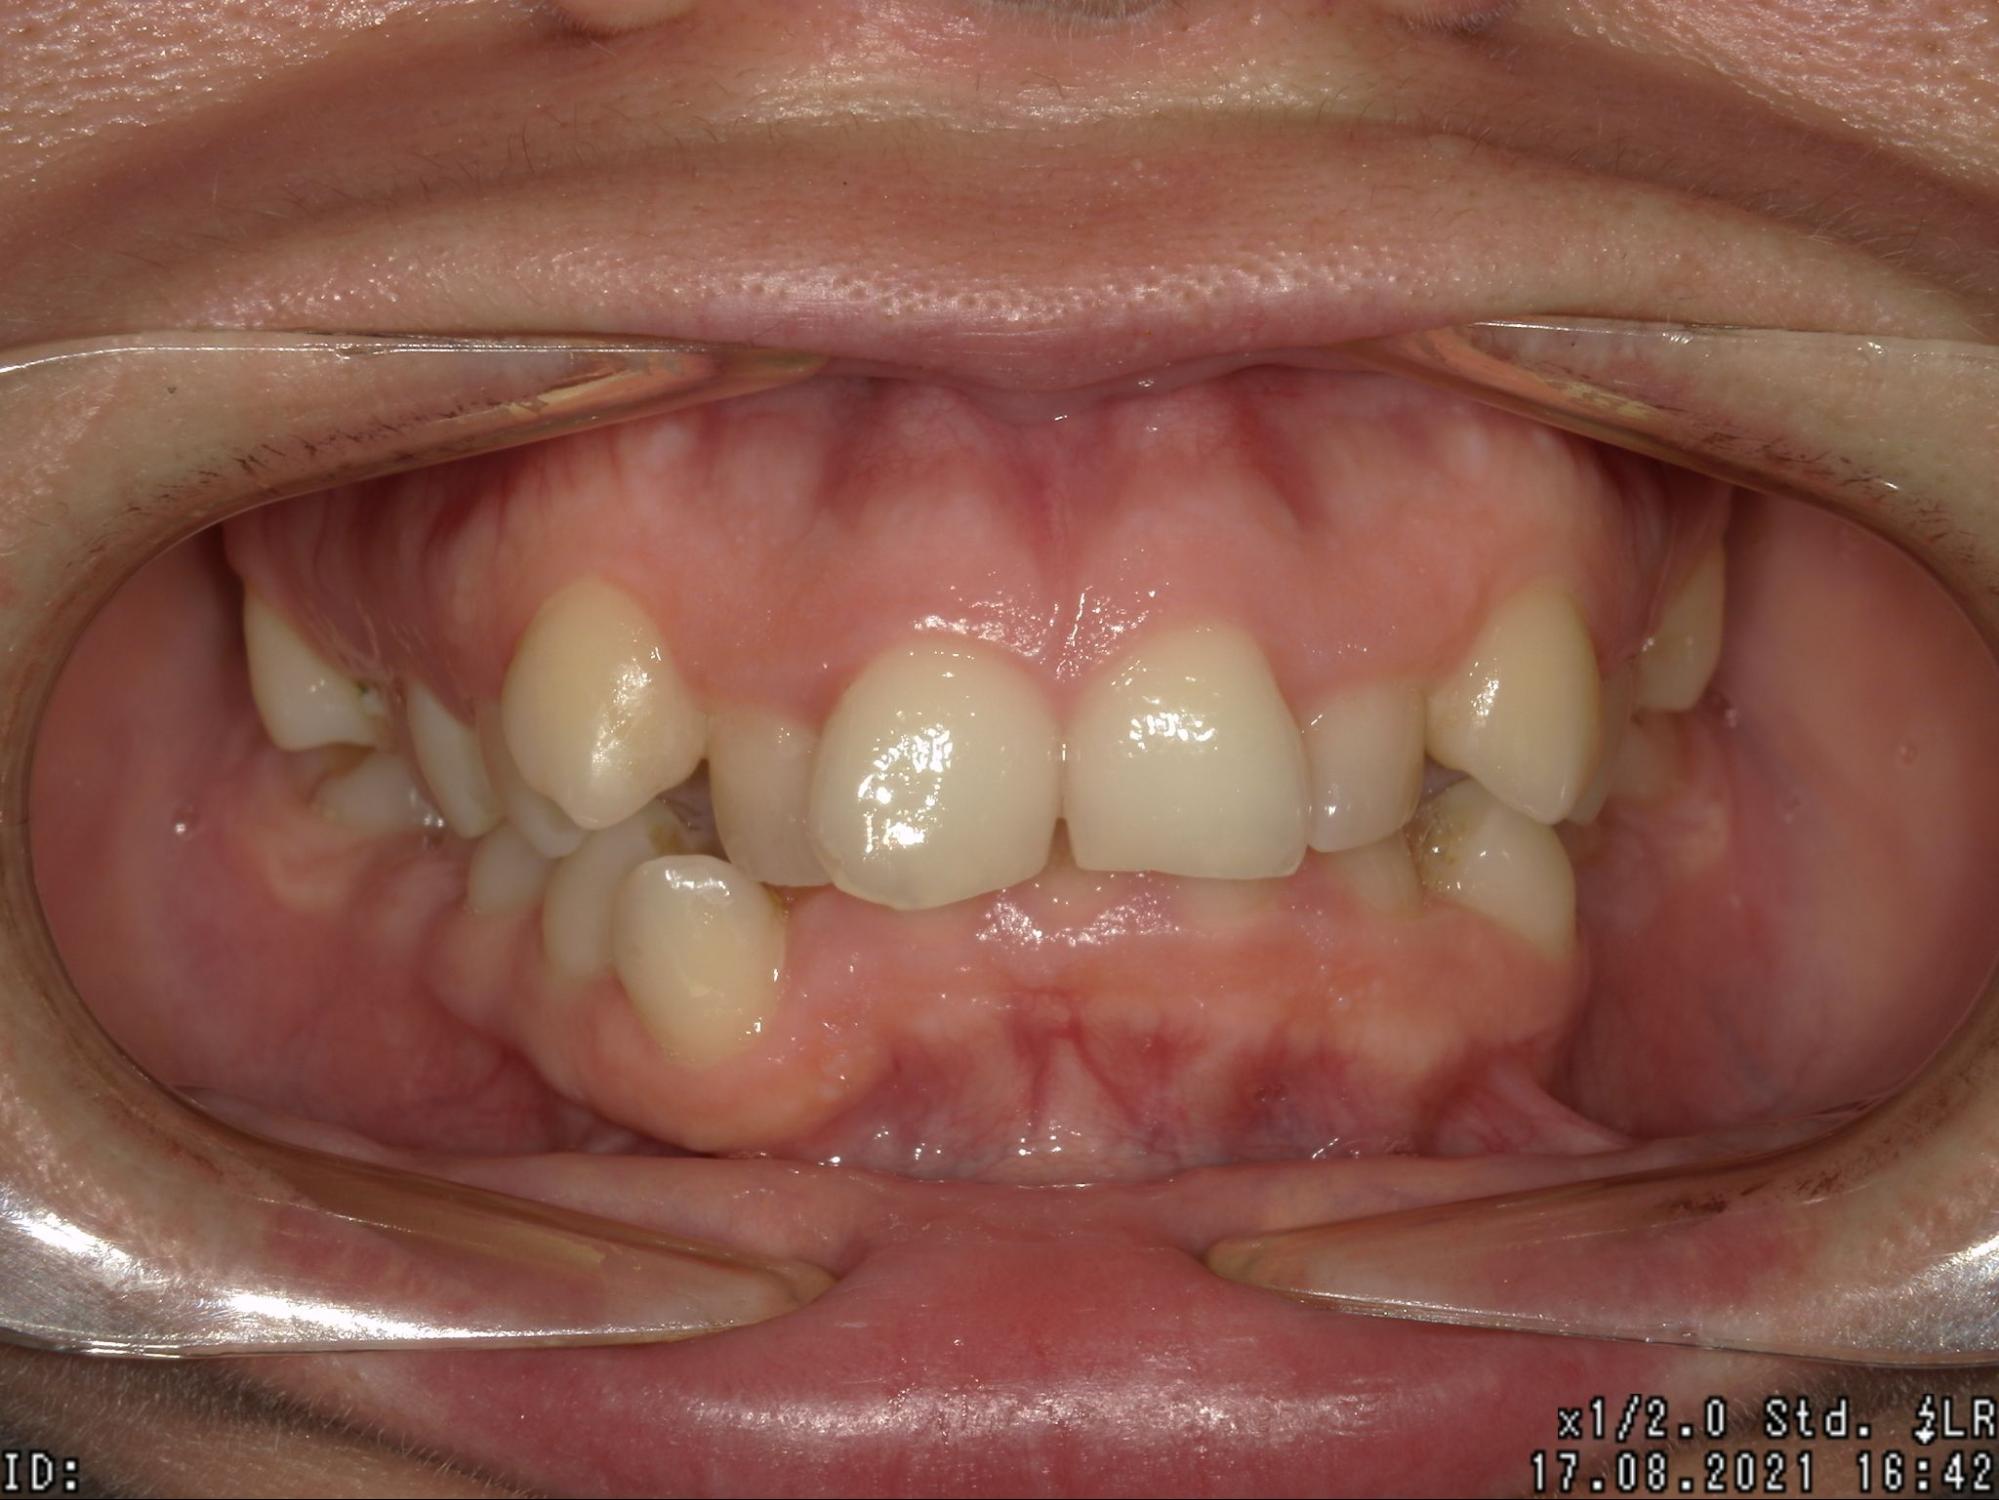

Клинический случай

В практике стоматолога-ортодонта Герасимовой Яны Олеговны есть интересный случай коррекции прикуса на элайнерах. Елена пришла на прием с жалобами на эстетику улыбки, затрудненное открывание рта, пережевывание пищи. Из-за неправильного положения зубов верхние центральные резцы травмировали десны в области нижних зубов, что приводило к частым воспалительным процессам, а также опущению уровня десны. Со временем это привело к формированию повышенной чувствительности зубов — резкой боли при действии холодного, кислого.

При обследовании было выявлено множество проблем. Во-первых, нижняя челюсть имела неправильную форму, была недоразвита. Во-вторых, зубы верхней челюсти занимали неправильное положение, был диагностирован глубокий прикус.

Было принято решение о лечении на элайнерах. После снятия цифровых слепков был составлен план, а Елена увидела, как будет выглядеть ее улыбка еще до начала лечения. Всего было изготовлено 36 капп, которые нужно было носить в течение 22 месяцев. В результате удалось:

• расширить нижнюю и верхнюю челюсть;

• нормализовать положение зубов;

• добиться правильного смыкания зубов;

• изменить в лучшую сторону черты лица, избавиться от второго подбородка;

• уменьшить выраженность носогубных складок;

• улучшить функцию жевания.